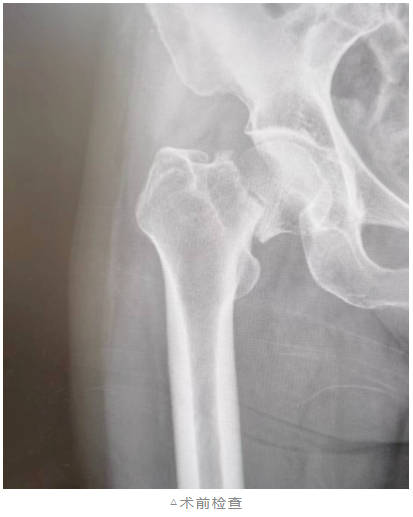

前不久,84岁的张奶奶不慎在家摔了一跤,当即感到疼痛难忍,无法正常活动,立即被家人送往我院骨科诊治。

“考虑患者年龄大、体质弱,如果采取常规后外侧及外侧手术入路会对肌肉等组织损伤较大,出血多,术后疼痛感较重。”骨科主任杨春生向患者及家属解释说,“综合患者病情及身体状况,建议选择髋关节置换DAA微创前侧入路。”

患者家属同意手术方案后,经过充分的术前准备,骨科团队医生们选择前侧入路进行髋关节置换,切口仅有一根手指长度,从肌间隙进入,只需离断一根动脉分支,不会损伤肌肉。